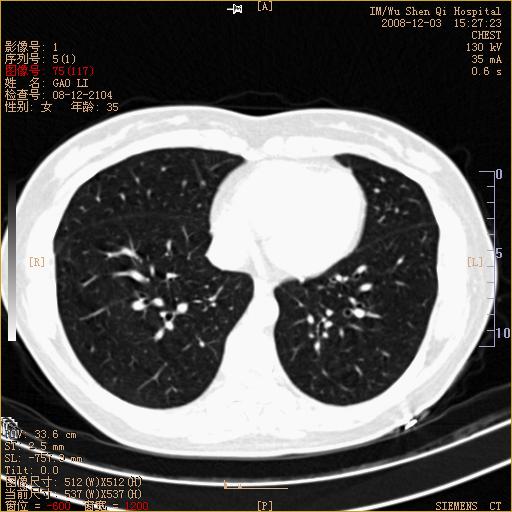

标题: CT16895:女,35岁,反复咳嗽数月,只传部分图像,是否考虑 [打印本页]

标题: CT16895:女,35岁,反复咳嗽数月,只传部分图像,是否考虑

左下肺支扩

典型“印戒征”。

印戒征,支持支扩.

左下肺扩支

印戒征,支扩